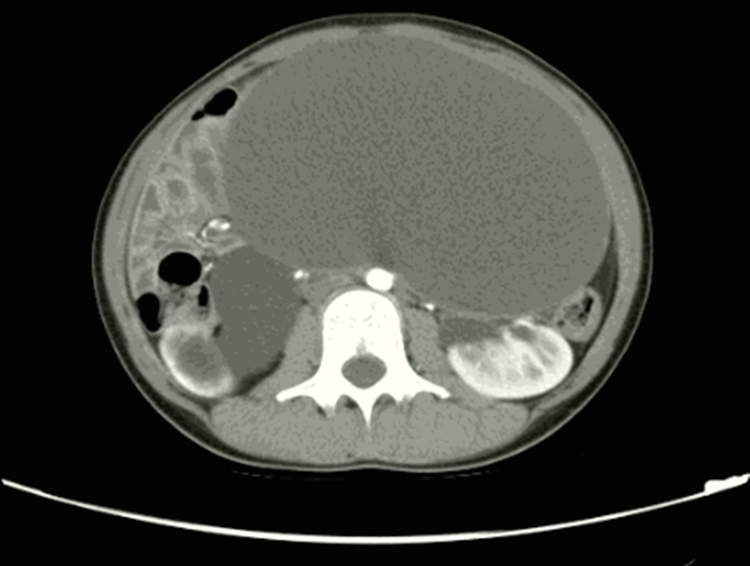

Các bác sĩ Bệnh viện Đa khoa Quảng Ninh ngày 26/1, cho biết kết quả siêu âm, chụp cắt lớp vi tính phát hiện khối u buồng trứng dạng nang chiếm toàn bộ ổ bụng dưới bệnh nhân. Khối u kích thước lớn, dài 30 cm, to tương đương với bụng bầu khoảng 6 tháng, chèn ép các tạng trong ổ bụng, gây giãn đài bể thận phải.

Khối u dạng nang kích thước lớn chiếm toàn bộ ổ bụng dưới của bệnh nhân. Ảnh: Bệnh viện cung cấp